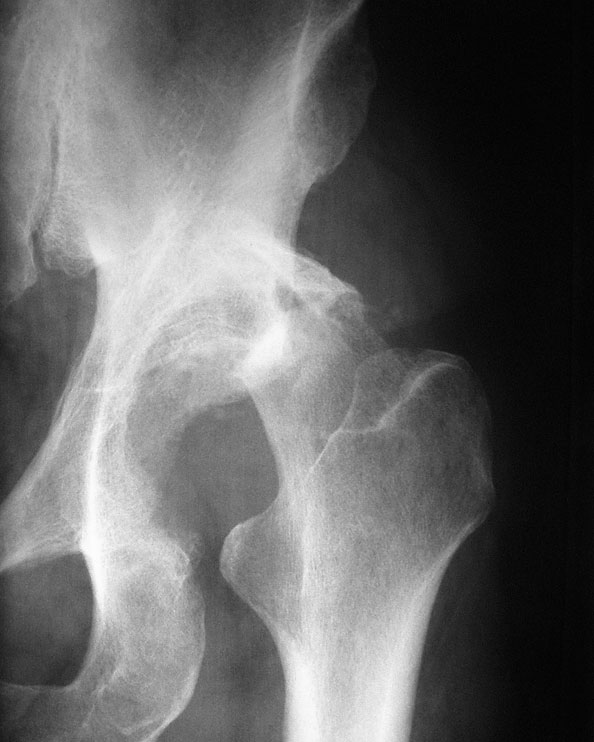

Атеросклероз тазобедренного сустава